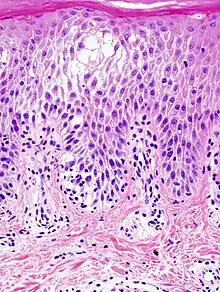

La spongiose résulte d'un mécanisme entraînant la dissociation des cellules de l'épiderme, et s'accompagnant d'une production de liquide, qui forme des vésicules et qui s'écoule en dehors après rupture de celles-ci. La spongiose est un signe caractéristique de l'eczéma et des dermatites spongiformes (pityriasis rosé de Gibert, parapsoriasis en petites plaques etc.).